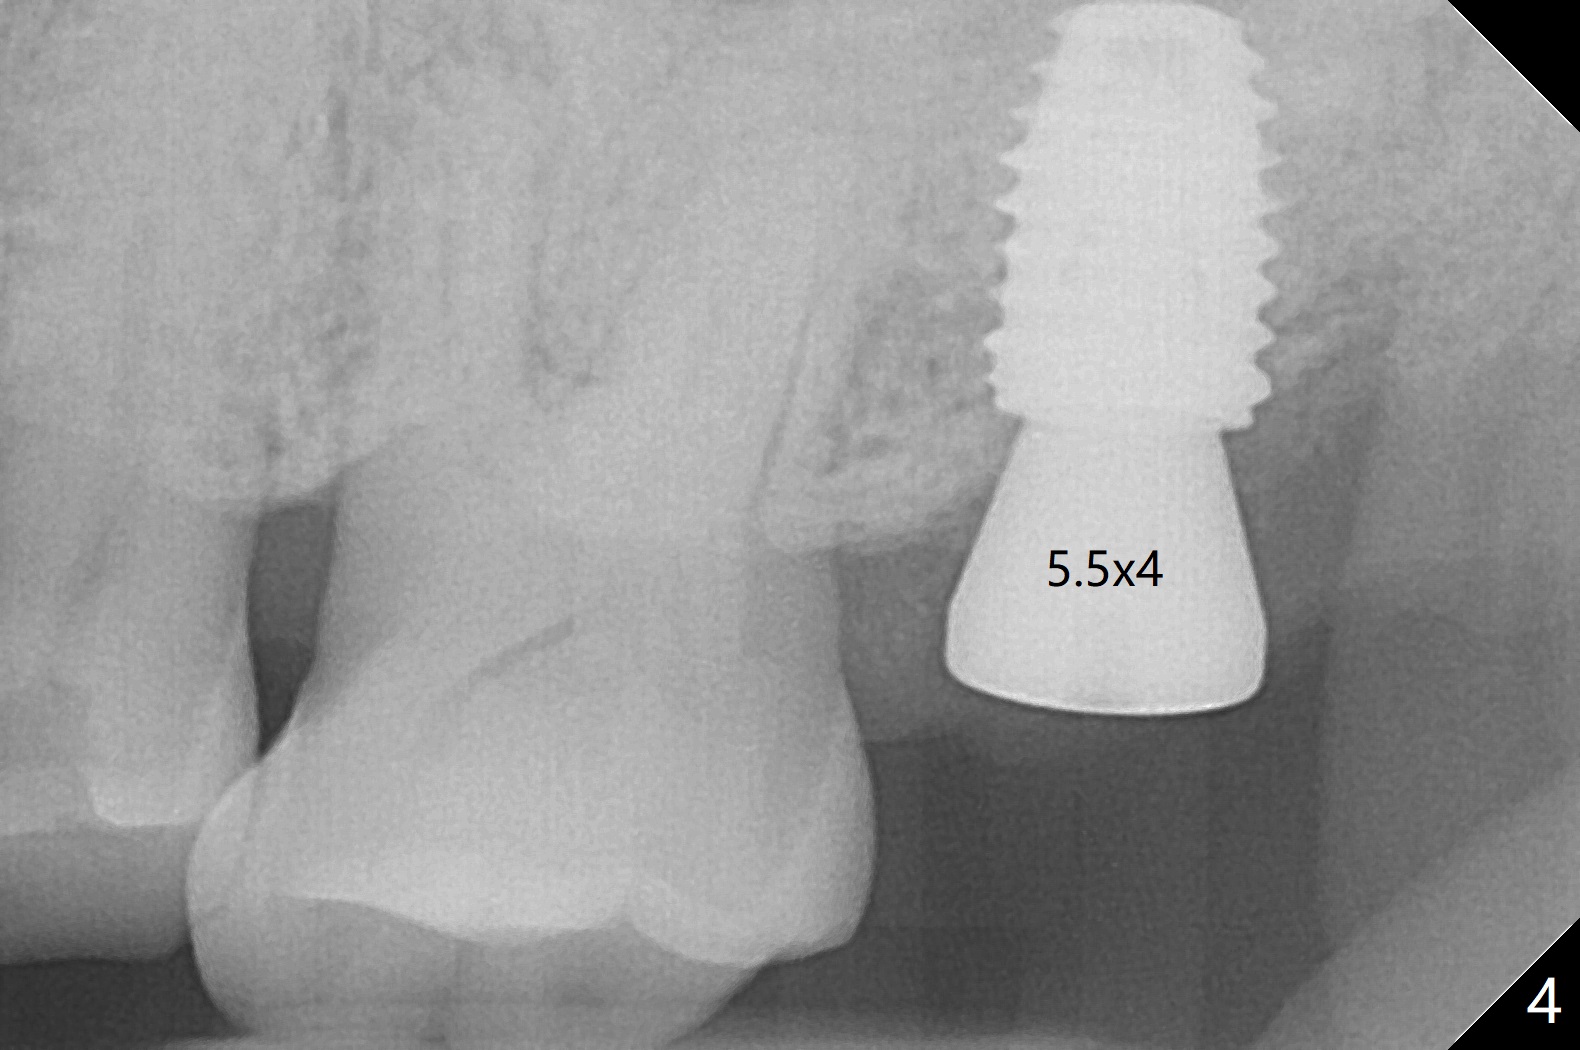

Following shorter drill sequence at #15, sinus round drills (18 and 19 mm long) are used to perforate the sinus floor without membrane tear. With autogenous bone for sinus lift (Fig.1 S), a 5x7.3 mm implant is placed with high torque in spite of using 5 mm cortical drill with 3 O-rings. Clinically there appears no hard tissue distal, although the bone density (graft bone in the 3rd molar socket) is low shown in bitewing (Fig.2 ^). Allograft is applied around the distal coronal portion of the implant before placement of Osteogen Plug and 4-0 PGA suture (Fig.3 *). Profile drill is required during uncover. With sensor I, there is less distortion and angulation (Fig.4, as compared to Fig.1 (sensor II)). A 5.5 mm profile drill is used prior to healing abutment placement.